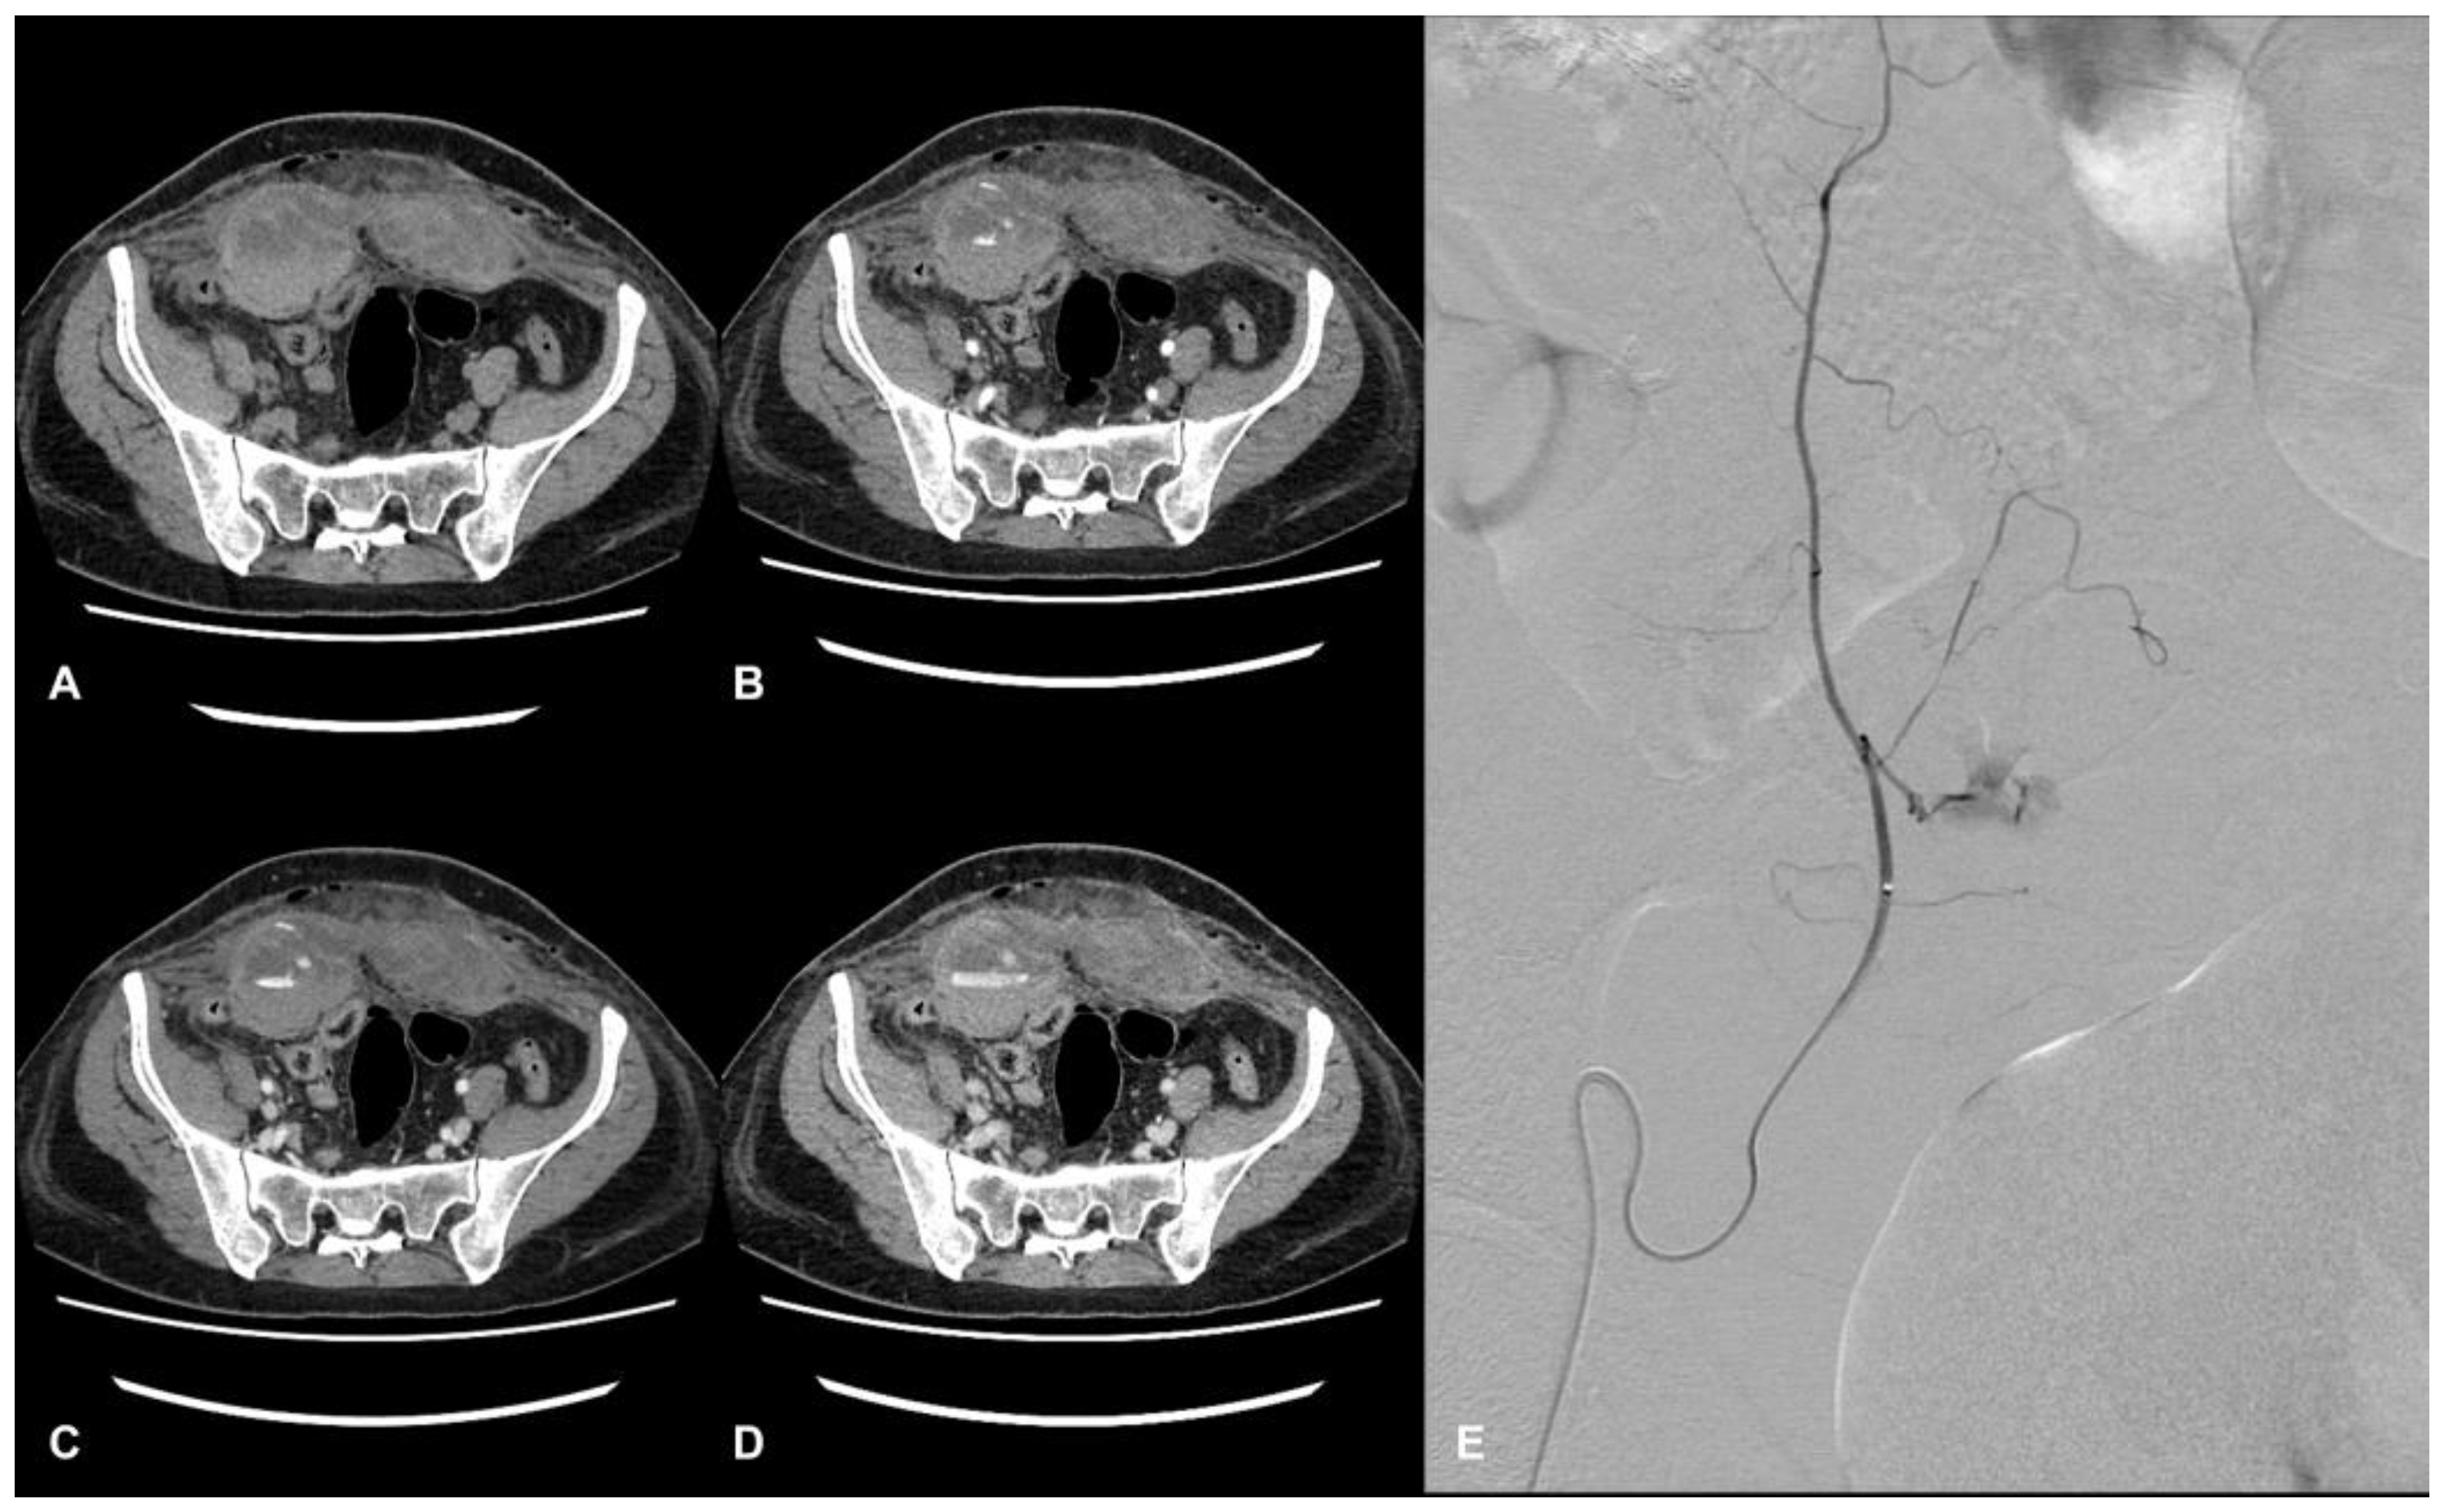

Diagnosing AWHs can be challenging since signs and symptoms are often nonspecific. In this scenario, computed tomography angiography (CTA) is recognized as the gold standard for identifying and characterizing hematomas, allowing for determining the localization of the bleeding site, the extension and the dimensions of the hematoma, and the exclusion of other acute abdominal diseases (Figure 1) [7].

Figure 1.

CT and DSA images of a hospitalized patient with COVID-19. Evidence of a large hematoma within rectus abdominis below the arcuate line in axial CT images. The pre-contrast phase shows the extension and location of the hematoma, showing a fluid level (hematocrit effect) (A). The contrast-enhanced acquisition at the arterial (B), portal (C), and delayed phase (D) show active bleeding within the hematoma. Angiography shows a contrast blush from branches of the right inferior epigastric artery (E).

In COVID-19 patients, Polyaev et al. report that some specific CT signs, such as the presence of a fluid level (hematocrit effect) and the phenomenon of a “signal flare”, in the context of spontaneous hematoma, correlate with active bleeding on DSA, indicating endovascular treatment is needed [11]. The management and the treatment of AWHs can include conservative, endovascular, or surgical approaches; in hemodynamically stable patients with life-threatening AWHs, catheter-directed angiography and embolization have become the primary options for treatment [2].